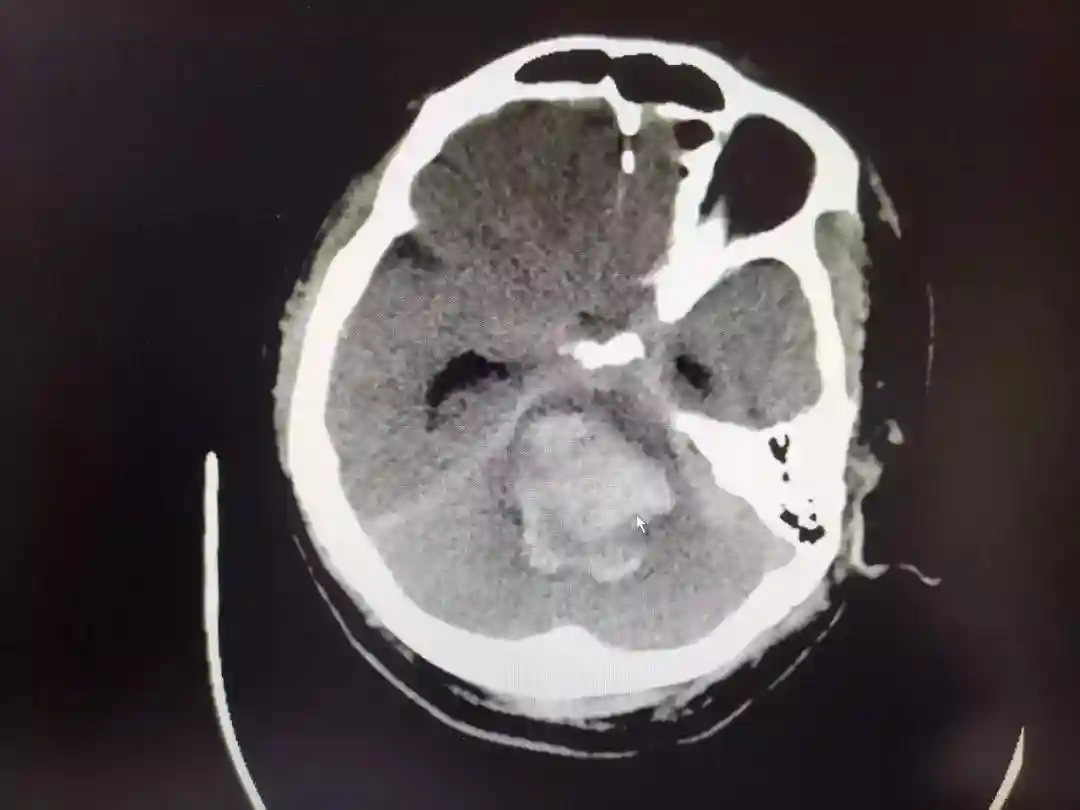

因为头颅CT的结果无疑宣判了患者的死刑,大量的脑干出血!

脑干出血是脑出血中最为凶险危重的一种,病死率非常高!

有不完全的统计数据表明,脑干出血达到3毫升的死亡率便高达70%,出血量在5毫升以上的死亡率更是高达90%,如果出血量超过10毫升便几乎是神仙难救了。

而这位患者的出血量显然要远远超过10毫升!

为什么脑干出血会如此重要凶险?

因为脑干是生命的中枢,通俗的说因为它包含着延髓、桥脑、中脑、网状系统等主管着呼吸、心率、血压、体温等生命体征变化的重要部位。